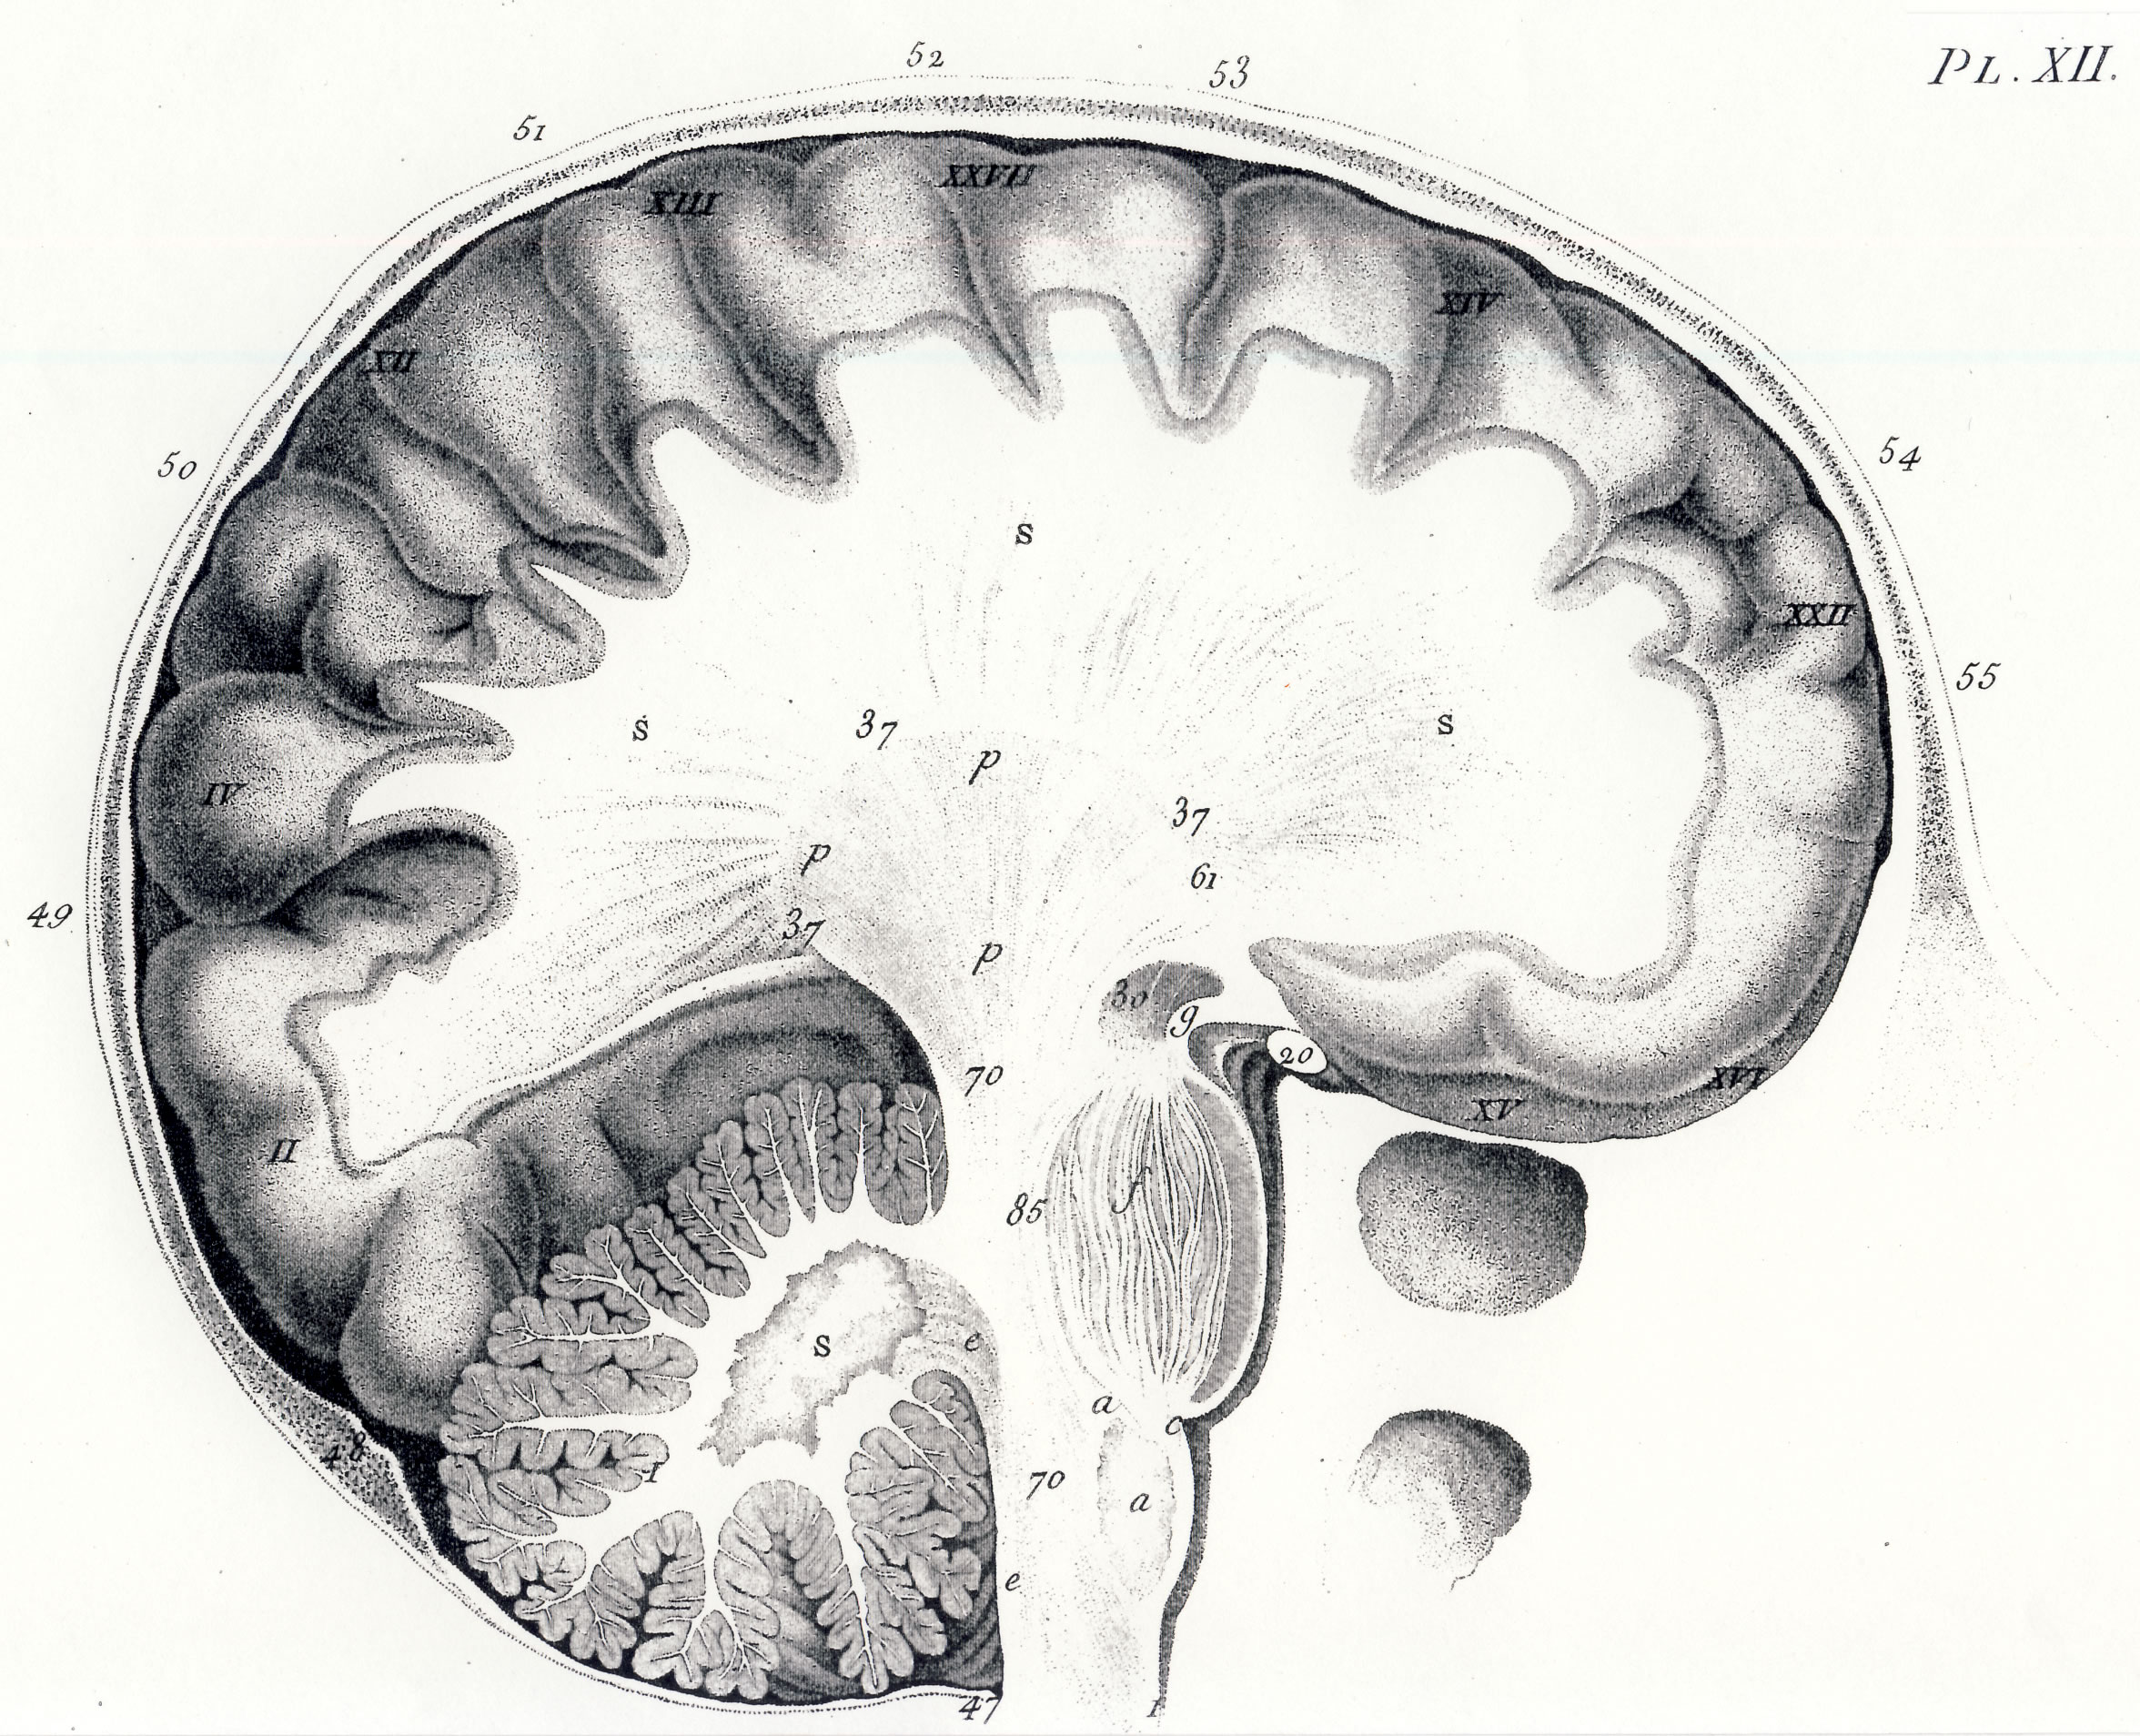

Gall: Plates

Gall, F. J. (1818). Anatomie et physiologie du système nerveux en général, et du cerveau en particulier, Avec des observations sur la possibilité de reconnoître plusieurs dispositions intellectuelles et morales de l´homme et des animaux, par la configuration de leurs têtes.

Librairie Grecque-Latine-Allemande, Vol. 3, I-XXXV u. 1-379 100 planches.